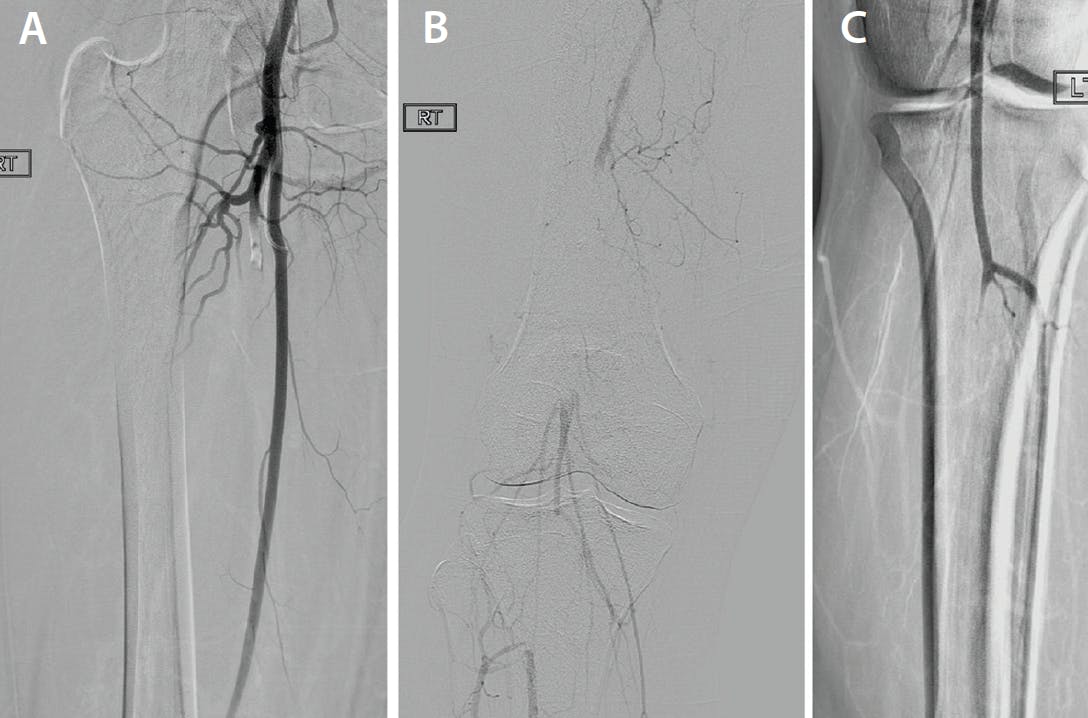

The patient was found to have bilateral embolization that caused an occlusion of the descending branch of the right profunda femoral artery, right popliteal artery occlusion, and left tibioperoneal trunk occlusion (Figure 1).

Figure 1. Baseline arteriogram of right profunda femoral artery (A), right popliteal artery (B), and left tibioperoneal trunk (C) occlusions.